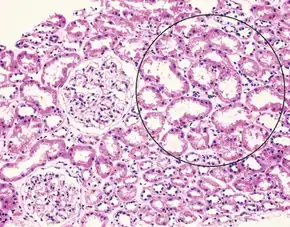

| Liver histology is altered in HRS while kidney histology is normal. The upper image is a trichrome stain (chicken wire appearance) of cirrhosis of the liver, the most common cause of HRS. | |

Those affect usually have cirrhosis, severe alcoholic hepatitis, or liver failure, with onset when liver function deteriorates rapidly because of a sudden insult such as an infection, bleeding in the gastrointestinal tract, or overuse of diuretics. Deteriorating liver function is believed to cause changes in the circulation that supplies the intestines, altering blood flow and blood vessel tone in the kidneys. The kidney failure of HRS is a consequence of these changes in blood flow, rather than direct damage to the kidney. Diagnosis is based on laboratory tests, Two types have been defined: type 1 entails a rapidly progressive decline in kidney function, while type 2 is associated with ascites (fluid accumulation in the abdomen) that does not improve with standard diuretics.

Many other diseases of the kidney are associated with liver disease and must be excluded before making a diagnosis of hepatorenal syndrome. Individuals with pre-renal kidney failure do not have damage to the kidneys, but as in individuals with HRS, have kidney dysfunction due to decreased blood flow to the kidneys. Also, similarly to HRS, pre-renal kidney failure causes the formation of urine that has a very low sodium concentration. In contrast to HRS, however, pre-renal kidney failure usually responds to treatment with intravenous fluids, resulting in reduction in serum creatinine and increased excretion of sodium.[3] Acute tubular necrosis (ATN) involves damage to the tubules of the kidney, and can be a complication in individuals with cirrhosis, because of exposure to toxic medications or the development of decreased blood pressure. Because of the damage to the tubules, ATN affected kidneys usually are unable to maximally resorb sodium from the urine. As a result, ATN can be distinguished from HRS on the basis of laboratory testing, as individuals with ATN will have urine sodium measurements that are much higher than in HRS; however, this may not always be the case in cirrhotics.[5] Individuals with ATN also may have evidence of hyaline casts or muddy-brown casts in the urine on microscopy, whereas the urine of individuals with HRS is typically devoid of cellular material, as the kidneys have not been directly injured.[3] Some viral infections of the liver, including hepatitis B and hepatitis C can also lead to inflammation of the glomerulus of the kidney.[18][19] Other causes of kidney failure in individuals with liver disease include drug toxicity (notably, the antibiotic gentamicin) or contrast nephropathy, caused by intravenous administration of contrast agents used for medical imaging tests.[3]